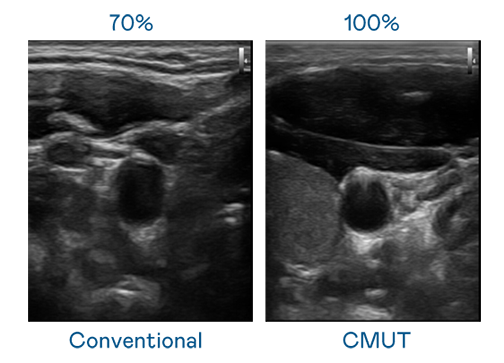

CMUT 技术是一种用电容式微机电元件来产生超音波讯号的技术。与传统 PZT 压电式技术相比,CMUT 频宽增加 30%,更宽频的超音波讯号让影像解析度大幅提升,是实现高影像品质医疗超音波扫描、促进精准医疗发展的关键技术。

大频宽带来超清晰影像

超音波影像的解析度高低,首先取决于探头能发出的讯号频宽。彩虹多多 CMUT 可提供高清晰的超音波讯号,提供高频宽、高灵敏度、影像纹理细节更高的超音波影像,协助医护人员缩短影像判读时间及利用精准的医疗影像进行诊断。